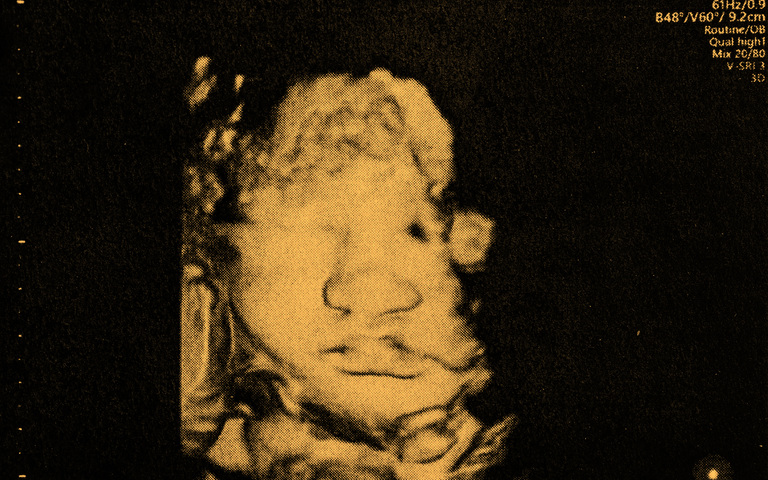

Was machen Babys alles im Bauch der Mutter? – Video geht viral

21 Millionen Views

Ein virales Video auf X (ehemals Twitter) zeigt, was Babys im Mutterleib alles tun.